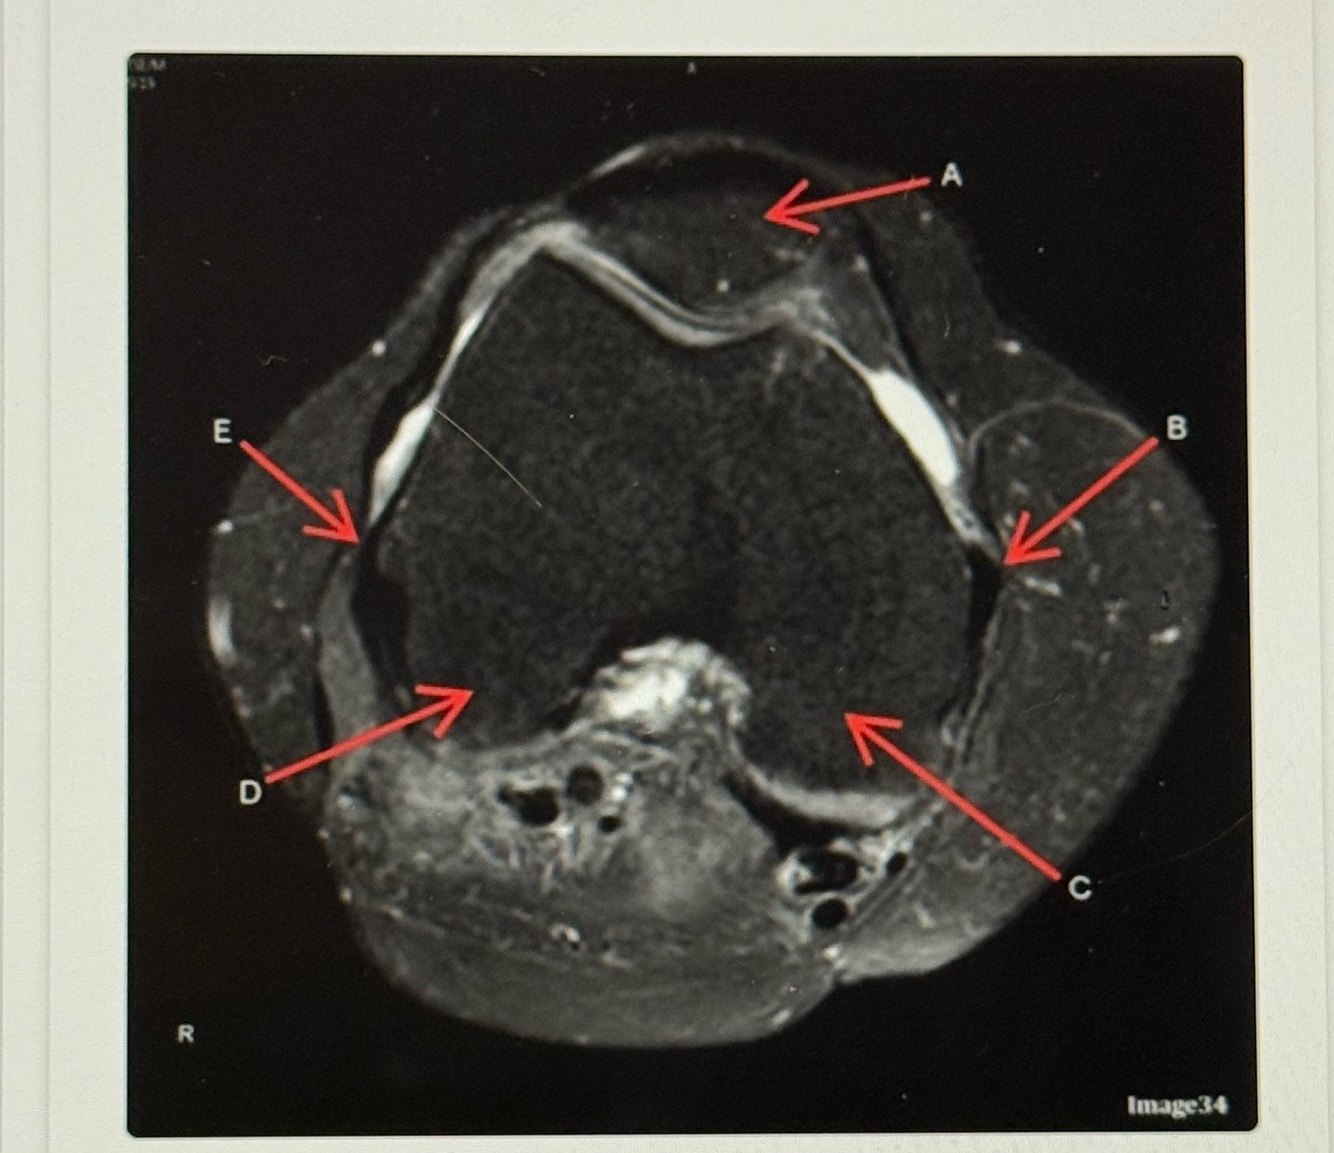

Letter A points to the

Letter B points to the

A

Medial

Collateral ligament (MCL)

Q

Letter E points to the

Lateral collateral ligament (LCL)